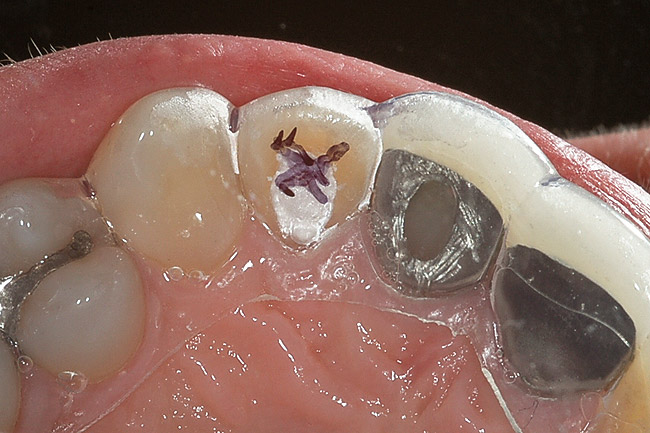

Figure 1  A clinical examination demonstrates a single, very dark lateral incisor and a moderately dark central incisor with a crown on the adjacent central incisor and several dark gingival areas.

Figure 1

The first and most important consideration is to determine the cause of the tooth discoloration. A clinical examination is conducted, which includes evaluation of the color of the teeth and the adjacent gingiva (Figure 1). Additionally, transillumination, radiographs, and pulp testing may be appropriate. Radiographs should always be taken of a single dark tooth, as teeth can undergo pulpal necrosis without any other symptom than becoming dark (Figure 2). From this examination, the determination is made of whether the tooth is vital or not. A vital tooth may be darker due to trauma and resultant bleeding into the dental tubules without loss of vitality. Vital teeth may also discolor from internal or external resorption, calcific metamorphosis, as well as decay or leaking restorations on the proximal or lingual surfaces. A non-vital tooth may have become darker from the same reasons as a vital tooth, but also have experienced pulpal death. A tooth that has received endodontic treatment may also later darken, especially if there is a poor seal of the endodontic access opening (Figure 3).